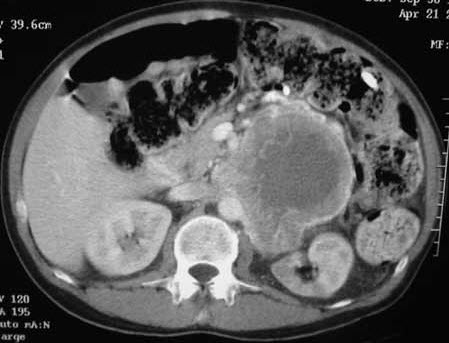

Abdominal CT with contrast demonstrates an 87 3 116-mm necrotic, partially enhancing mass in the region of the left adrenal gland (Figure 1). Chest CT with contrast reveals multiple bilateral noncalcified pulmonary nodules with no other apparent lesions in the thorax.